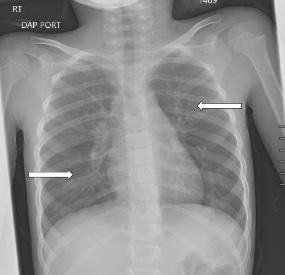

The patient was referred to both cardiology and pulmonology for outpatient evaluation by her primary care physician four months after her hospitalization. Her chief complaints at these follow-up visits included decreased oxygen saturation readings at home, dyspnea on exertion, decreased appetite, and fatigue. Cardiology performed a cardiac ultrasound, which was normal, and did not believe her symptoms were cardiac in nature. A CXR obtained five months later demonstrated increased perihilar and peribronchial markings bilaterally and mild reticular nodular opacity involving both lungs (Image 4). She was diagnosed with moderate persistent reactive airway disease which, per her treating pulmonologist, was likely a sequela of her acute lung injury from inhalation of the cake luster dust. At greater than one year since hospitalization, she continued to be prescribed budesonide/ formoterol twice daily and rescue albuterol as needed.

4. Chest radiograph at five months after discharge demonstrating increased perihilar and peribronchial markings bilaterally and mild reticular nodular opacity involving both lungs (arrows).